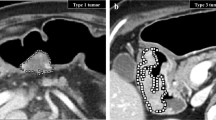

In this retrospective study, 215 patients (average age: 57 years (18–87 years)) who received nCRT for LARC between June 2005 and December 2016 and underwent a staging diagnostic portal venous phase CT were identified. The patients were randomly divided into two datasets: a training set (n = 170), and a validation set (n = 45). Tumor heterogeneity was assessed on the CT images using fractal dimension (FD) and filtration-histogram texture analysis. In the training set, the patients with pCR and non-pCR were compared in univariate analysis. Logistic regression analysis was applied to identify the predictive value of efficacy of nCRT and receiver operating characteristic analysis determined optimal cutoff value. Subsequently, the most significant parameter was assessed in the validation set.